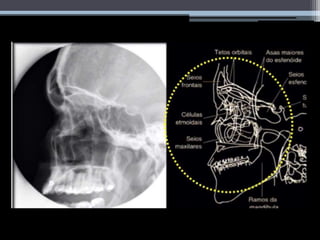

Radiografia Convencional

Incidências

Radiográficas

Mentonaso

(Waters)

Perfil Axial de Hirtz

Linhas do crânio

• - Auxiliam no posicionamento em exames de

crânio e face.

Mentonaso (Waters)

Variante da incidência de Waters-

Incidência de Blondeau

Em crianças:

Perfil

Sentado ou em Ortostatismo

Axial de Hirtz

• #12 Auxiliam no posicionamento em exames de crânio e face. São formadas por entre dois pontos de reparo anatómico, as principais usadas nesse exame são as que estão na imagem.

• #13 -Também chamado seios da face PA -Posicionar a testa e o nariz encostados na mesa ou estativa, manter a linha orbitomeatal (LOM) perpendicular ao filme, angular o raio central 15º caudais. Raio central deverá saír no násio.

• #14 Seios frontais projectados na sutura frontonasal. Células etmoidais anteriores visualizadas lateralmente a cada osso frontal, directamente abaixo de cada seio frontal. Alinhamento da crista petrosa no terço inferior da órbita.

• #15 -Estender o pescoço do paciente com queixo apoiado na mesa ou estativa. O nariz não deverá estar encostado Ajustar o crânio até que a linha mento meatal (LMM) esteja perpendicular ao filme ou receptor da imagem. Usar cilindro de extensão Raio central deve incidir nos ossos parietais e saír no acântion.

• #16 A mentonaso é melhor para a visualização dos seios maxilares, sendo também uteis para para os seios frontais. É importante a correcta angulação do paciente visando retirar a projecção do rochedo o que pode levar a falsa impressão de velamento ou nível liquido em seios maxilares. Uma variante desta incidência pode ser feita com a boca aberta (incidência de blondeau), permitindo a visualização do seio esfenoidal através da projeção do palato.

• #17 Uma variante desta incidência pode ser feita com a boca aberta (incidência de blondeau), permitindo a visualização do seio esfenoidal através da projeção do palato.

• #18 -Em crianças deve sempre ter se em mente a idade de formação dos seios paranasais: ao nascimento para as células etmoidas e antro maxilar, 2 a 3 anos para o seio maxilar, 5 a 7 anos para os seios frontais e 12 anos para o seio esfenoidal

• #19 -Paciente deitado em posição de nadador ou paciente em ortostatia. Posicionar o crânio em perfil absoluto Raio central direcionado para um ponto cerca de 5cm superior ao MAE – ponto médio entre o angulo do olho e MAE.

• #20 Pode ser visualizado o seio frontal, o seio esfenoidal, maxilar as células etmoidais e a sela turca em perfil. E o tecto da orbita. E ramos mandibulares e seios maxilares em perfil ABSOLUTO!!!!!!!

• #21 Sinonimos: submento vértice Paciente sentado ou em decúbito dorsal. Elevar o queixo superextendendo o pescoço até que a linha infra orbito meatal (LIOM) ESTEJA PARALELA Á MESA. A CABEÇA DEVE ESTAR APOIADA NO VÉRTICE DO CRANIO. CUIDADO PARA NÃO HAVER ROTAÇÃO. RAIO CENTRAL PERPENDICULAR Á LIOM, CENTRADO A UM PONTO MÉDIO ENTRE OS ANGULOS MANDIBULARES.

• #22 Seios maxilares, esfenoidais, células etmoidais, fossas nasais. Pirâmides petrosas visualizadas simetricamente.